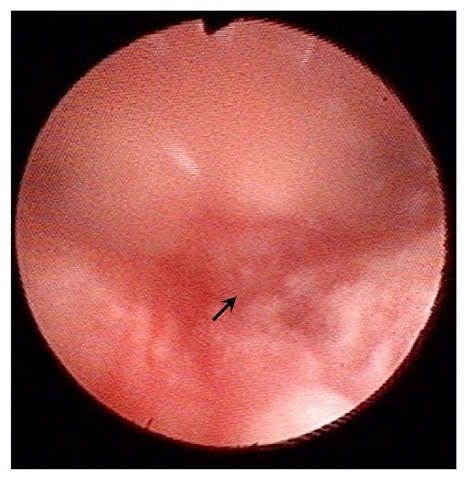

子宮內膜刺激手術 2016 最新 國際認證 證明 是可以增加試管嬰兒成功率胚胎著床率,但是大部分病人會痛However, the endometrial injur...